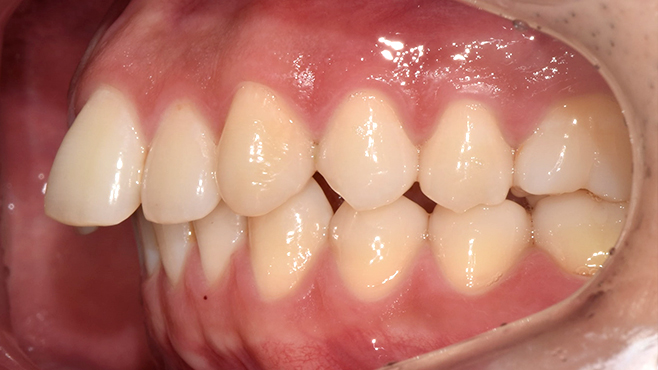

맞는 건 괜찮은데… 충치는 못 참겠습니다|20대 격투기 선수 치과 방문기

2026.02.06